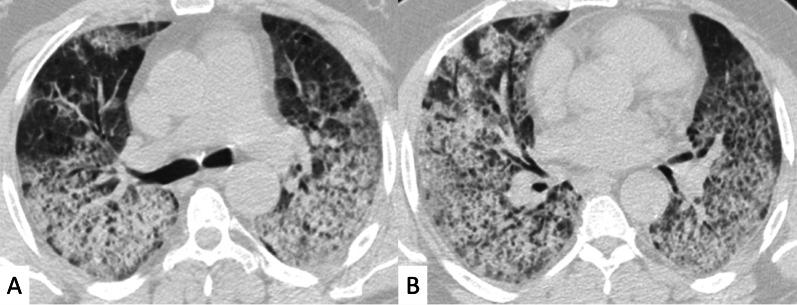

Connective tissue diseases (CTDs) include a spectrum of disorders that affect the connective tissue of the human body; they include autoimmune disorders characterized by immune-mediated chronic inflammation and the development of fibrosis. Lung involvement can be misdiagnosed, since pulmonary alterations preceded osteo-articular manifestations only in 20% of cases and they have no clear clinical findings in the early phases. All pulmonary structures may be interested: pulmonary interstitium, airways, pleura and respiratory muscles. Among these autoimmune disorders, rheumatoid arthritis (RA) is characterized by usual interstitial pneumonia (UIP), pulmonary nodules and airway disease with air-trapping, whereas non-specific interstitial pneumonia (NSIP), pulmonary hypertension and esophageal dilatation are frequently revealed in systemic sclerosis (SSc). NSIP and organizing pneumonia (OP) may be found in patients having polymyositis (PM) and dermatomyositis (DM); in some cases, perilobular consolidations and reverse halo-sign areas may be observed. Systemic lupus erythematosus (SLE) is characterized by serositis, acute lupus pneumonitis and alveolar hemorrhage. In the Sjögren syndrome (SS), the most frequent pattern encountered on HRCT images is represented by NSIP; UIP and lymphocytic interstitial pneumonia (LIP) are reported with a lower frequency. Finally, fibrotic NSIP may be the interstitial disease observed in patients having mixed connective tissue diseases (MCTD). This pictorial review therefore aims to provide clinical features and imaging findings associated with autoimmune CTDs, in order to help radiologists, pneumologists and rheumatologists in their diagnoses and management.

结缔组织病(CTDs)包括一系列影响人体结缔组织的疾病;它们包括以免疫介导的慢性炎症和纤维化发展为特征的自身免疫性疾病。肺部受累可能会被误诊,因为肺部改变仅在20%的病例中先于骨关节炎表现出现,且在早期阶段没有明确的临床发现。所有肺部结构都可能受累:肺间质、气道、胸膜和呼吸肌。在这些自身免疫性疾病中,类风湿关节炎(RA)的特征是普通型间质性肺炎(UIP)、肺结节和伴有空气潴留的气道疾病,而系统性硬化症(SSc)常表现为非特异性间质性肺炎(NSIP)、肺动脉高压和食管扩张。NSIP和机化性肺炎(OP)可见于多发性肌炎(PM)和皮肌炎(DM)患者;在某些情况下,可观察到小叶周围实变和反晕征区域。系统性红斑狼疮(SLE)的特征是浆膜炎、急性狼疮性肺炎和肺泡出血。在干燥综合征(SS)中,HRCT图像上最常见的表现是NSIP;UIP和淋巴细胞间质性肺炎(LIP)的报道频率较低。最后,纤维化NSIP可能是混合性结缔组织病(MCTD)患者中观察到的间质性疾病。因此,本图像综述旨在提供与自身免疫性CTDs相关的临床特征和影像学表现,以帮助放射科医生、呼吸科医生和风湿病科医生进行诊断和管理。